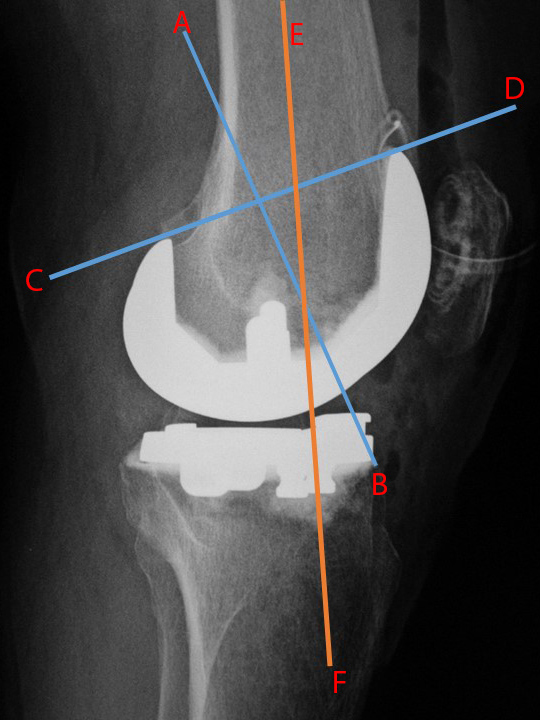

| Total Knee arthroplasty (TKA) Evaluation |

| 67 year-old woman. Postoperative images of a Biomet XPA Bicruciate Preserving TKA. Same patient as above. On the AP view (left image) the femorotibial angle is the intersection between the femoral anatomic axis (blue line) and the tibial anatomic axis (orange line). The femoral component should be centered along the femoral anatomic axis, and the tibial component should be perpendicular to the tibial anatomic axis. The femorotibilal angle should be 4-7° valgus. On the lateral view (right image) the femoral component should be roughly perpendicular to the femoral anatomic axis (orange line), and the tibial component should be perpendicular to the tibial anatomic axis (blue line) or have slight flexion (3°–6°) [posteriorly sloped]. |

Same patient as left two images. Another way to evaluate the TKA on the lateral view is to draw line C-D through anterior and posterior margins of the femoral component and line A-B perpendicular to line C-D. Line E-F is along the anatomic axis of the femur. The angle between lines A-B and E-F should approximate 30°. |